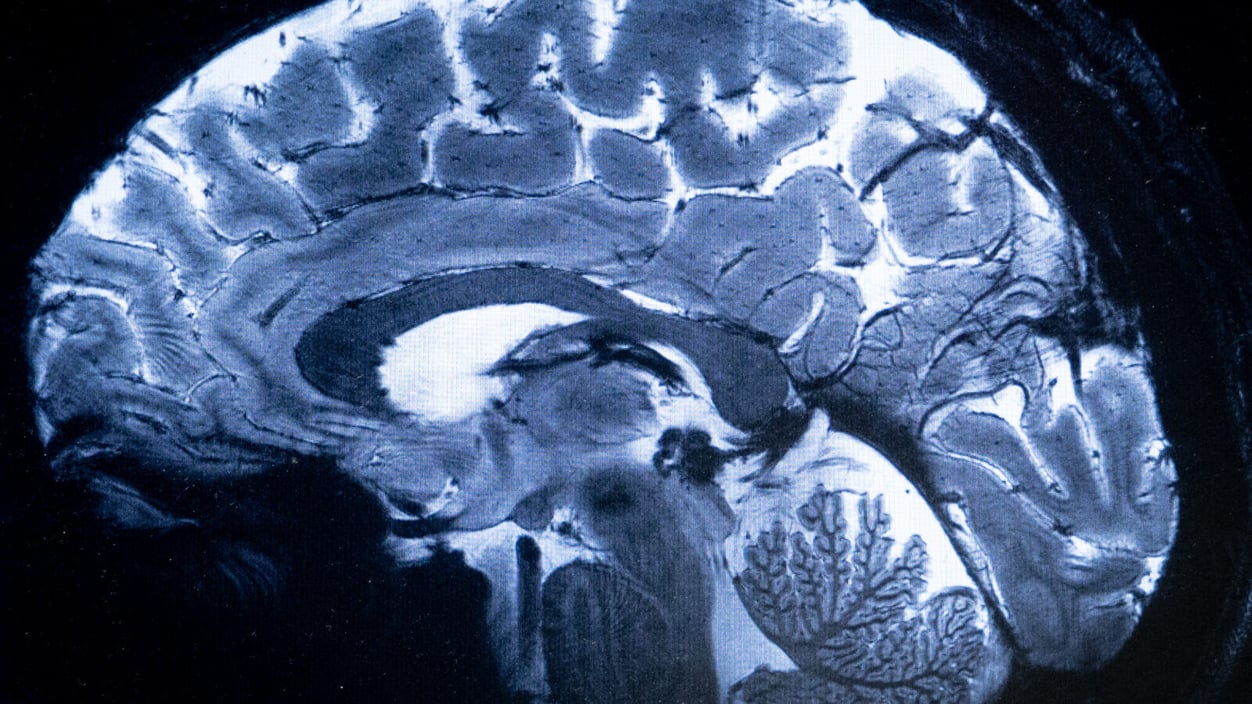

Most of us have never had our brains scanned. But a new generation of more affordable and highly portable MRI (pMRI) devices are rapidly reshaping neuroimaging research and clinical care. There could be a future out there in which people get regular brain "check-ups" from portable MRIs, write three authors of today's First Opinion essay.

To address the rise in neuroimaging, these authors suggest the creation of a new field: neuroimaging counseling. Like genetic counselors before them, neuroimaging counselors would be trained to help explain brain scan findings to patients. The clinical interpretation of scans would remain in the domains of radiology, neurology, and neurosurgery. But communicating those readings, addressing follow-up questions, and facilitating dialogue about the emotional weight of abnormal brain imaging results could be supported by counselors. Read more on what this new type of health care worker could do.